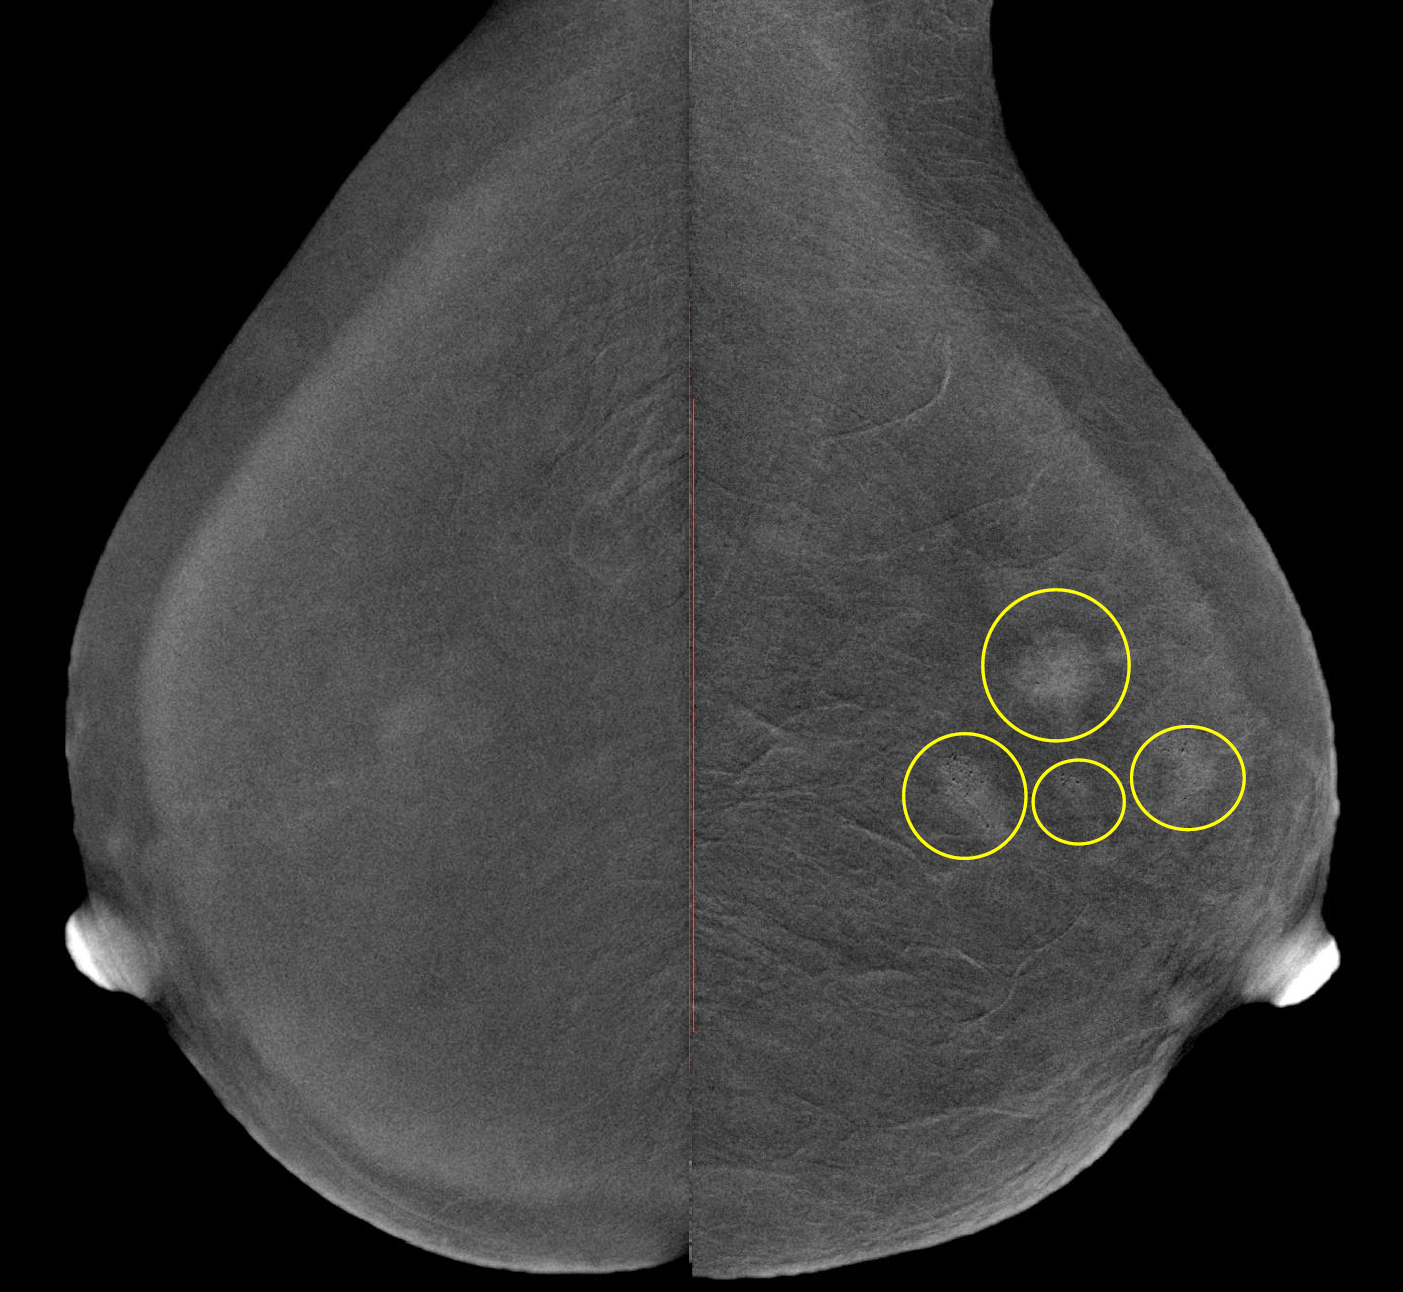

Шаг 8. Нужна ли функция цифрового томосинтеза (DBT)?